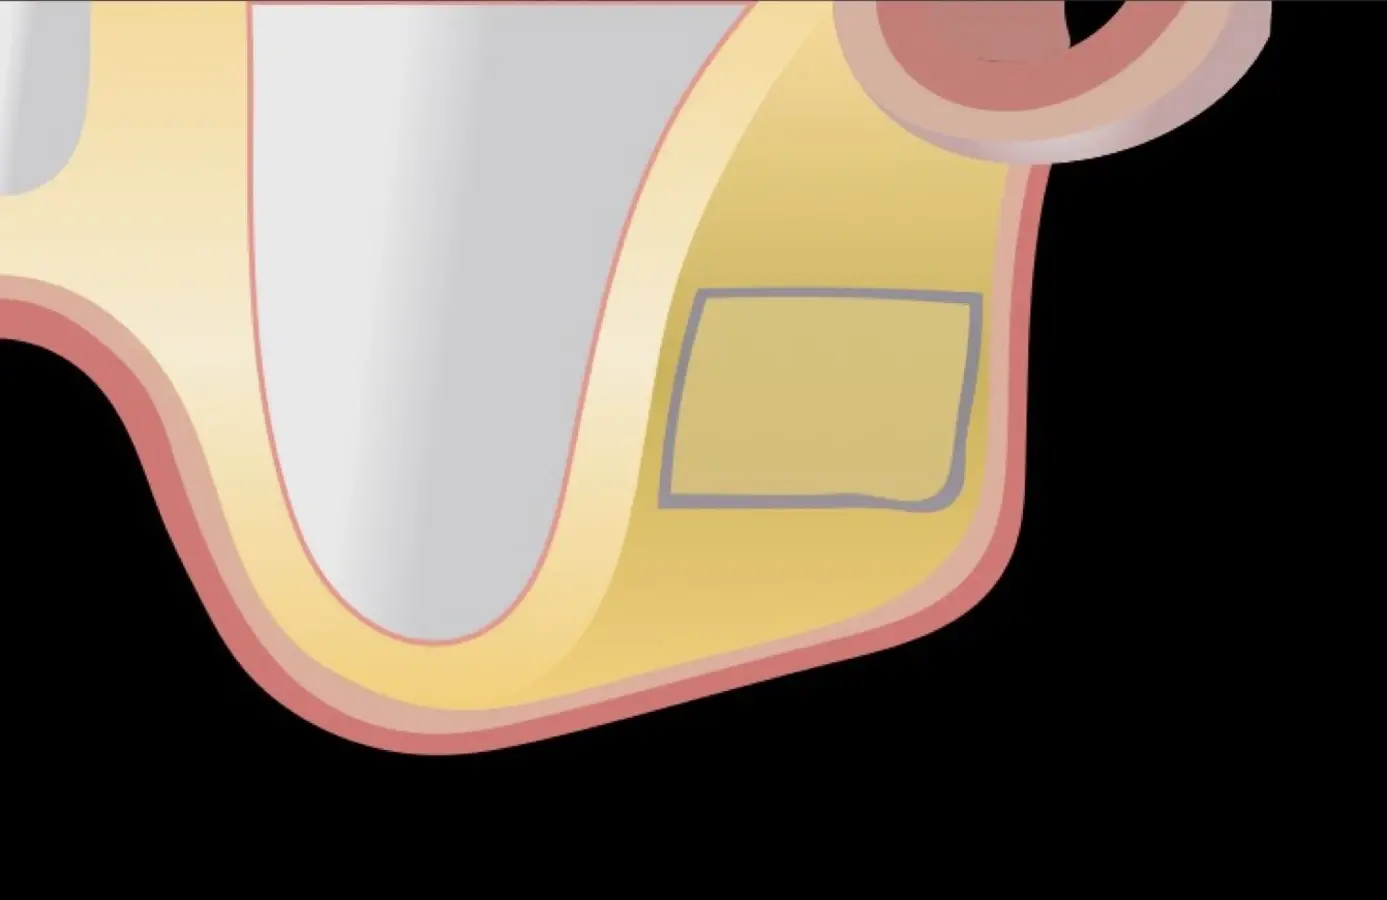

Figura 2. Espesor de la pared lateral (X), altura del reborde residual (Y), profundidad del seno maxilar (Z) y espesor de la membrana sinusal.

El tipo de inserto a ser utilizado dependerá del espesor de la pared ósea. Si la pared es menor a 0.5 mm, es mejor utilizar insertos de desgaste para prevenir la ruptura de la membrana de Schneider; si el espesor es mayor a 0.5 mm, se puede utilizar insertos de corte de espesor medio (Figura 3).